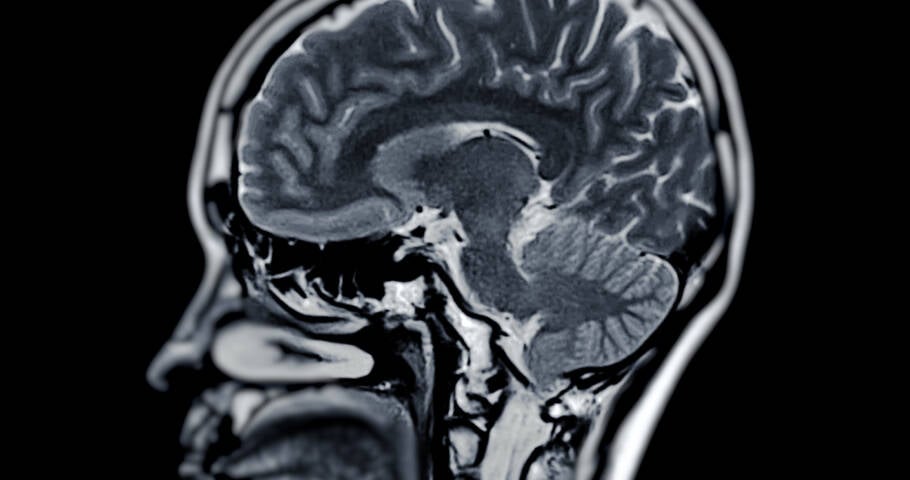

Um estudo realizado por cientistas suecos do Instituto Karolinska sugere que o uso de inibidores seletivos de recaptação de serotonina (ISRS), um dos antidepressivos mais prescritos globalmente, pode acelerar a perda de memória em pacientes com demência.

A pesquisa analisou dados de quase 19.000 pacientes com demência, com idade média de 78 anos. Destes, cerca de 20% faziam uso de antidepressivos, sendo os ISRS os mais comuns (65%). Os pacientes foram acompanhados por um período médio de quatro anos, durante o qual suas capacidades cognitivas foram monitoradas por meio de testes de memória.

Os resultados indicaram que aqueles que tomavam antidepressivos tiveram uma redução adicional de 0,3 pontos por ano em um teste de memória de 30 pontos, em comparação com os que não utilizavam tais medicamentos. Especificamente para os ISRS, essa redução foi ainda maior, chegando a 0,39 pontos extras por ano, e alcançando 0,42 pontos para aqueles que tomavam doses mais altas.